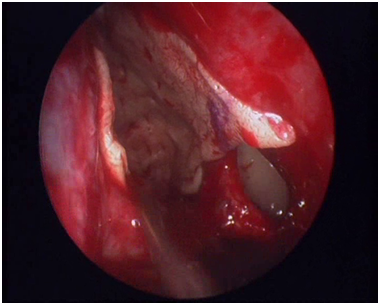

Using the same instruments, every ethmoid septum attached to the skull base and the lamina papyracea is gradually removed. This will serve a dual purpose: It will render the bed to receive the graft smooth and it will facilitate the removal of the mucosa. In order for the skin graft to survive, no remnant of nasal mucosa is left covering the lamina papyracea, the fovea ethmoidalis and the lateral surface of the middle and upper concha. The mucosa is meticulously removed making use of the round knife used in the ear surgery (Figure 4). The mucosa of the lateral surface of the middle and upper concha is removed making use of the microdebrider. The last action taken before the insertion of the graft is to suture-fix the middle concha to the septum with an absorbable stitch.

Figure 4 The use of the otosurgical round knife.